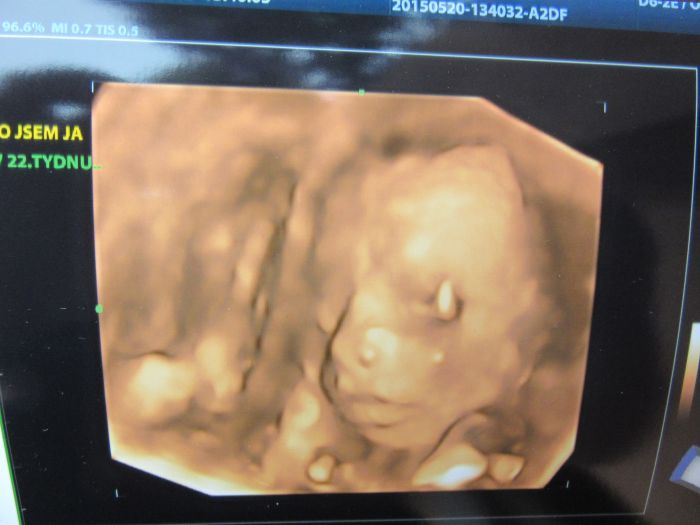

Ahojky, tak dneska jsme byli s manželem na 3D a máme potvrzenou malou fešandu. I přesto, že jsme si přáli kluka tak nakonec jsem spokojená, že to bude holčička. Doktor nám taky řekl, že je vše v pořádku a to je to hlavní. Přikládám fotečky, jsem z malý opravdu nadšená.

[744686] jakoby se na tebe divala, krásné!

kacenko to je fakt nadherna fotecka ,jak je tam krasne videt no uzasny:-) gratuluji k holcicce